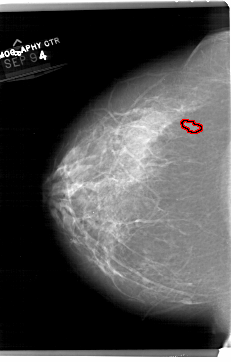

A_1514_1.LEFT_MLO

LEFT_MLO LINES 6871 PIXELS_PER_LINE 4501 BITS_PER_PIXEL 12 RESOLUTION 43.5 OVERLAY

FILE: A_1514_1.LEFT_MLO.OVERLAY

TOTAL_ABNORMALITIES 1

ABNORMALITY 1

LESION_TYPE MASS SHAPE IRREGULAR MARGINS ILL_DEFINED

ASSESSMENT 4

SUBTLETY 2

PATHOLOGY BENIGN

TOTAL_OUTLINES 1

BOUNDARY